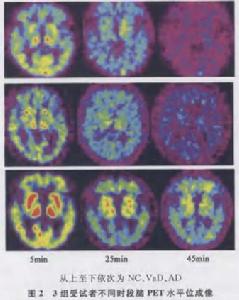

1.阿爾茨海默病(AD)AD起病隱匿,進展緩慢,記憶等認知功能障礙突出,可有人格改變,神經影像學表現為顯著的腦皮層萎縮,Hachacinski缺血量表≤4分(改良Hachacinski缺血量表≤2分)支持AD診斷。